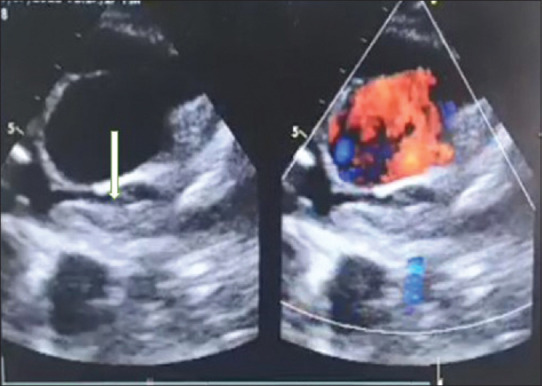

glenn后血栓形成是一种罕见的、需要立即关注的严重并发症,在资源有限的环境中,这种并发症并不罕见,因为患者往往无法随访,并且药物依从性差。这种罕见的并发症在过去很少有报道。我们描述了一个病例的一个巨大的血栓栓塞事件,在病人提出急性失代偿状态14年后,最初的姑息Glenn分流。我们报告了一种创新的策略,使用经导管机械取栓,使用旋转取栓装置和化学溶栓来成功拯救格伦电路。

PostGlenn thrombosis is an infrequent, serious complication requiring immediate attention, which is not uncommon in a resource-limited setting where patients are often lost to follow-up and have poor compliance with medications. This rare complication has infrequently been reported in the past. We describe a case of a massive thromboembolic event in a patient presenting acutely in a decompensated state 14 years after initial palliation by Glenn shunt. We report an innovative strategy of using transcatheter mechanical thrombectomy using a rotational thrombectomy device and chemical thrombolysis for the successful salvation of the Glenn circuit.